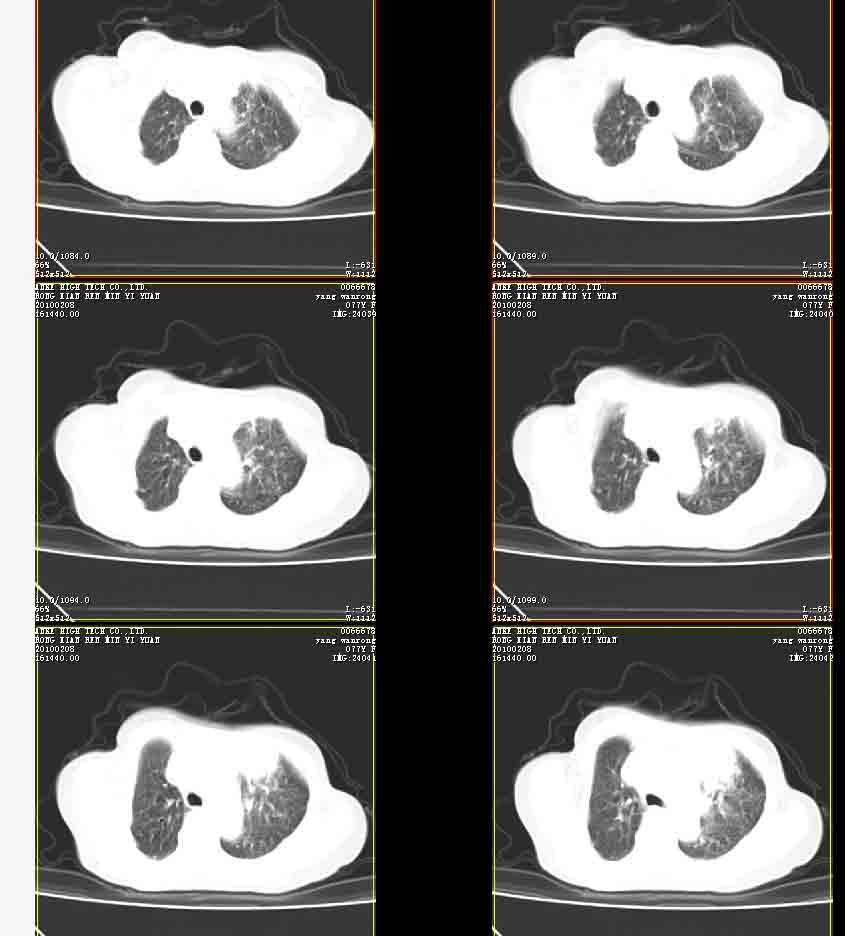

女77岁因左侧胸痛伴咳嗽入院;提示:病灶平扫45hu,强化145hu补充:双肺内未闻及干湿罗音

我的诊断意见:左肺上叶前段肺癌伴节段性不张。

在不张的肺内见到不规则的软组织,而且强化是不均匀的(该点可能是我的图像作得不好的原因)。

右肺近胸膜下区散在结节,性质?

请教左侧肺含气不良用什么解释更好?

左上肺前段可见分叶团块影,强化明显,周围见带状不张影,右肺结节,左肺沿肺纹模糊片状影,考虑左上肺占位,肺癌可能性大。

考虑左肺上叶前段肺癌伴节段性不张、肺内转移,建议薄层扫描。